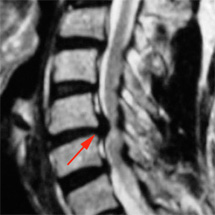

Die häufigsten Bandscheibenvorfälle werden an der Halswirbelsäule zwischen dem 5 und 6. und dem 6. und 7. Halswirbel gefunden und sind vorwiegend im hinteren Abschnitt des Faserrings lokalisiert, da dort kleine Narben von der ehemaligen Gefäßversorgung der Bandscheibe zurückgeblieben sind und deshalb der Faserring an dieser Stelle besonders schwach ist und leichter einreißen kann. Das herausgetretene Gewebe kann dann zu einer Irritation bzw. Druckschädigung des Rückenmarkes (man bezeichnet dies als Myelopathie) oder der aus dem Rückenmark abgehenden Spinalnervenwurzeln führen. Auch Fehlstellungen der Halswirbelsäule mit einer so genannten Steilstellung oder sogar Kyphose können resultieren. Dies führt dann zu einer Fehlbelastung der Wirbelgelenke und Muskeln.